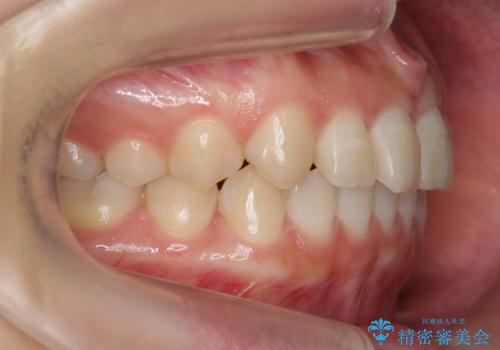

前歯のねじれ 乳歯を残して矯正治療

- 前歯のねじれを気にして来院。

左下に乳歯が残っていましたが、被せ物に穴が空いている状態でした。

乳歯は抜かずに保存的な治療を行いました。

上下の正中が1本分ずれていましたが、ちょうど1本分で目立たず、また、右下の歯が生まれつき少ないことを利用して、最小限の歯の移動にとどめました。